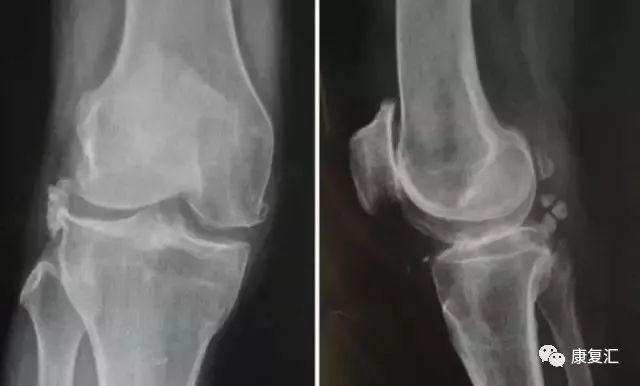

剥脱性骨软骨炎

关节内的骨软骨病,病因不明,关节软骨和软骨下骨变性和再钙化,最常见于股骨内髁,模糊的、定位不清的膝关节疼痛,有晨僵,反复的关节内积液(轻度)。如有游离体,可发生交锁症状。股四头肌萎缩,受累股骨髁关节软骨面压痛。

X线平片显示骨软骨病损或关节内游离体。如怀疑剥脱性骨软骨炎,摄片应包括前后位、后前隧道位、侧位和髌股关节切线位。